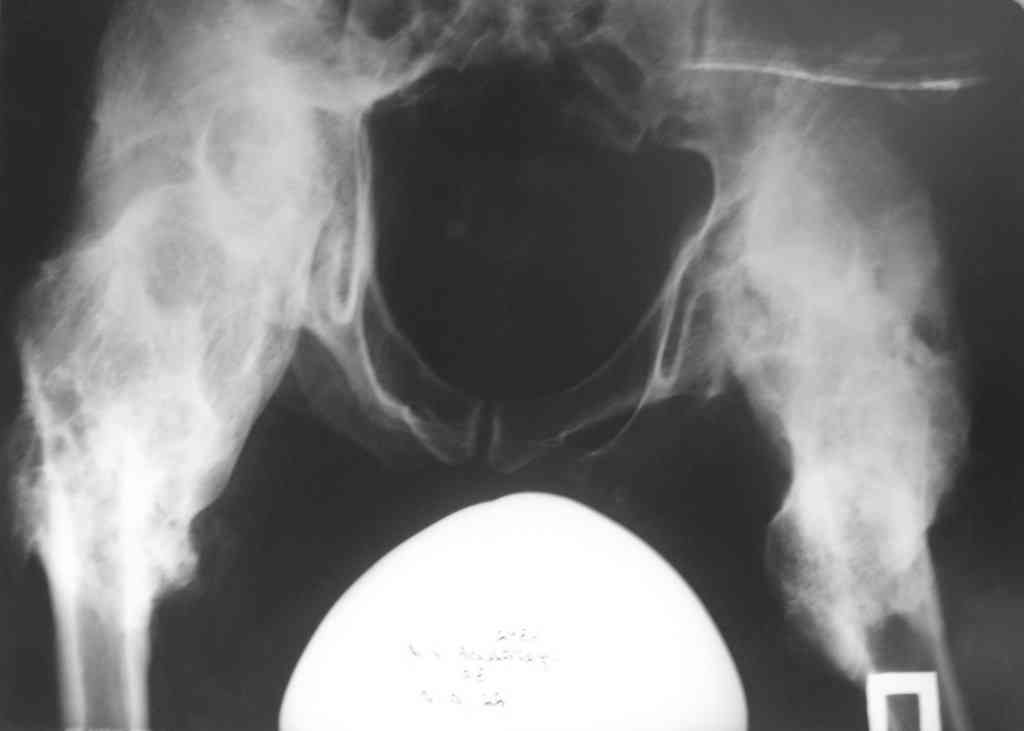

гетеротопическая оссификация области тазобедренных суставов |

Уважаемые коллеги! Больной после оскольчатого перелома С5 позвонка со сдавлением спинного мозга. Состояние после корпородеза С3-С7 пластиной (травма от 27.05.2007), после операции восстановился акт мочеиспускания и частично поверхностная и глубокая мышечно-суставная чувствительность. В течении 3 лет образовался оссификат, и день за днём ухаживать за больным становится все труднее. Если кто-нибудь сталкивался с подобными больными, или имеет информацию о методике лечения таких оссификатов, то будем рады Вашим советам. Можно ли произвести остеотомии в проксимальном отделе бедра с целью улучшения качества жизни больного(к примеру удобство персаживатся на кресло, коляску и.т.д) Заранее благодарен.

Не сталкивался,действительно редкое осложнение.Только почему Вы назвали гетеротипичным оссификатом?Тут полная перестройка вертельной зоны,шеек,головок бедер,вертлужных впадин..

Интересно,а каков патогенез такой перестройки?У больного должен быть выраженный спастический нижний парез...-и что?Почему вдруг такое осложнение?

Осложнение у спинальников очень частое (до 70%), но такую выраженность не видел никогда. При первых признаках ГО у спинальников обычно назначают НСПВС (чаще индометацин 75 мг в сутки). Опционально: варфарин, бифосфонаты, пульсирующее магнитное поле, радиотерапия.

Потеря центральной иннервации приводит к дефициту (более вероятно) ингибиторов остеогенеза или к избытку проостеогенных факторов, в результате чего мезенхимальные стволовые клетки встают на путь остеогенеза. Однако конкретные факторы никем еще не выделены.

Простая остеотомия вряд ли поможет - через пару месяцев все срастется в прежнем положении. Пересечь кость и зафиксировать в положении сгибания - получается что сидеть он будет хорошо, а лежать - только на спине с согнутыми ногами. Эндопротезы - дорого, результат малопредсказуем. Может максимальная резекция периартикулярных оссификатов, остеотомия по линии бывшего сустава с пластикой мышцей или фасцией?